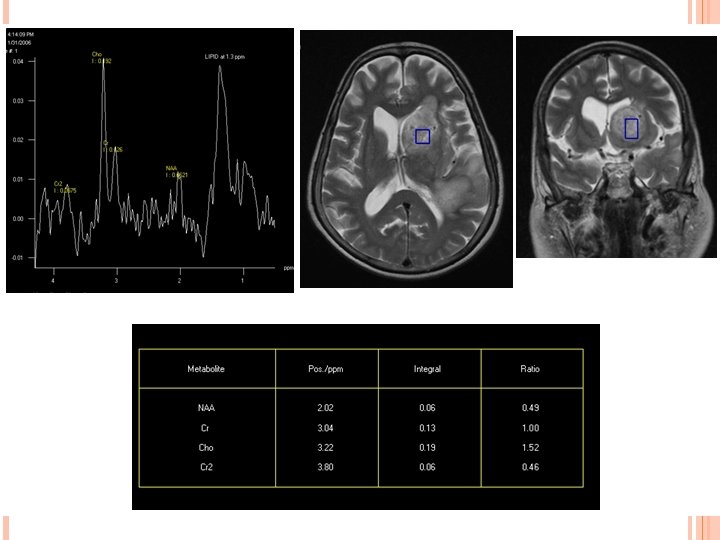

PRIMARY CNS LYMPHOMA IMAGING: CT-Typically a solitary hyperdense mass on NECT however multifocal in 50% cases. MR-Iso to hypointense on T 1 W and T 2 W image with diffusion restriction. Enhancement pattern are variable homogenous/heterogenous/ring like. Edema and mass effect in half of the lesion. Increase choline peak on MRS and increase Thallium uptake on SPECT.

Primary CNS lymphoma High choline peak. Lactate peak in necrotic component.